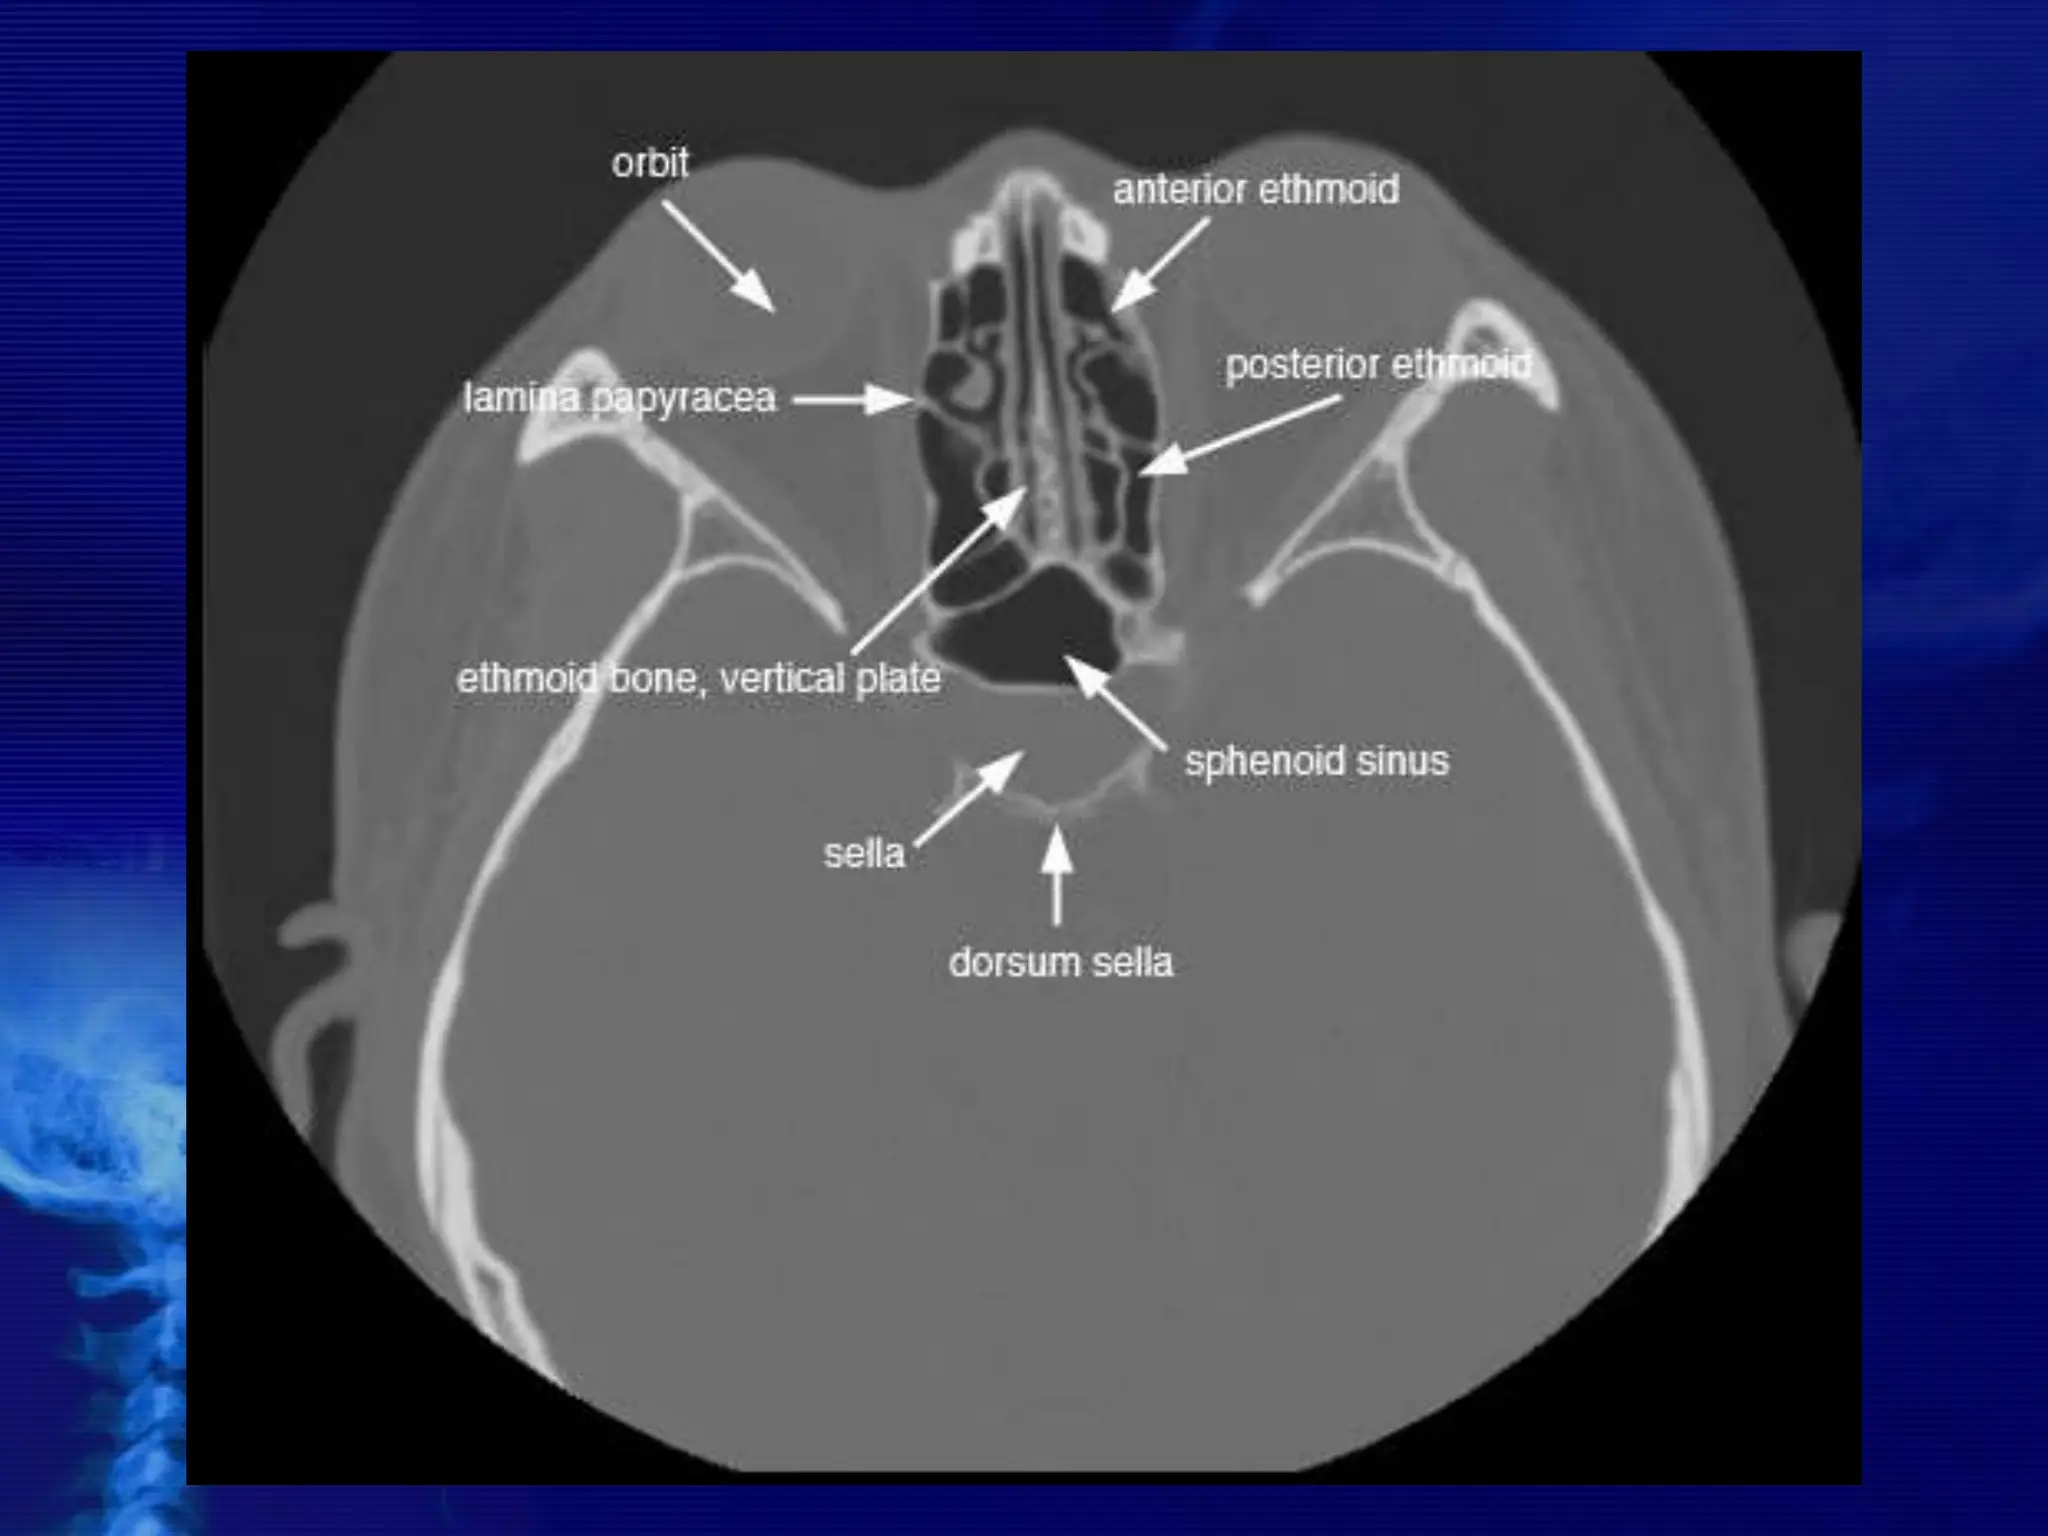

Ethmoid Sinuses

The ethmoid sinuses are contained within the lateral masses or

labyrinths of the ethmoid bone. These air cells are grouped into anterior,

middle, and posterior collections, but they all intercommunicate.

When viewed from the side, the anterior ethmoid sinuses appear to fill

the orbits. This occurs because portions of the ethmoid sinuses are

contained in the lateral masses of the ethmoid bone, which helps to form

the medial wall of each orbit.

Sphenoid Sinuses

The sphenoid sinuses lie in the body of the sphenoid bone directly below

the sella turcica. The body of the sphenoid that contains these sinuses is

cubic and frequently is divided by a thin septum to form two cavities. This

septum may be incomplete or absent entirely, however, resulting in only

one cavity.

CT NOSE

AND PNS

BASIC CONCEPTS

• CT scans typically obtained for visualizing the

paranasal sinus should include coronal and axial (3-

mm) cross

sections.

 Soft tissue and bony windows facilitate evaluation of

disease processes and the bony architecture.

 The use of intravenous contrast material just prior

to scanning can help define soft tissue lesions and

delineate vascularized structures, such as vascular

tumors.

 Contrast-enhanced CT is particularly useful in

evaluating neoplastic, chronic, and inflammatory

processes.

 The CT scan is the GOLD STANDARD

investigation in all preoperative cases as it

gives detailed bony anatomy of the area

and serves as a ‘road map’ for the

operating surgeon.

 CT scans are best done after a course of

antibiotics, so that acute inflammation is not

mistaken for chronic mucosal disease.

CROSS SECTIONAL ANATOMY –

AXIALS